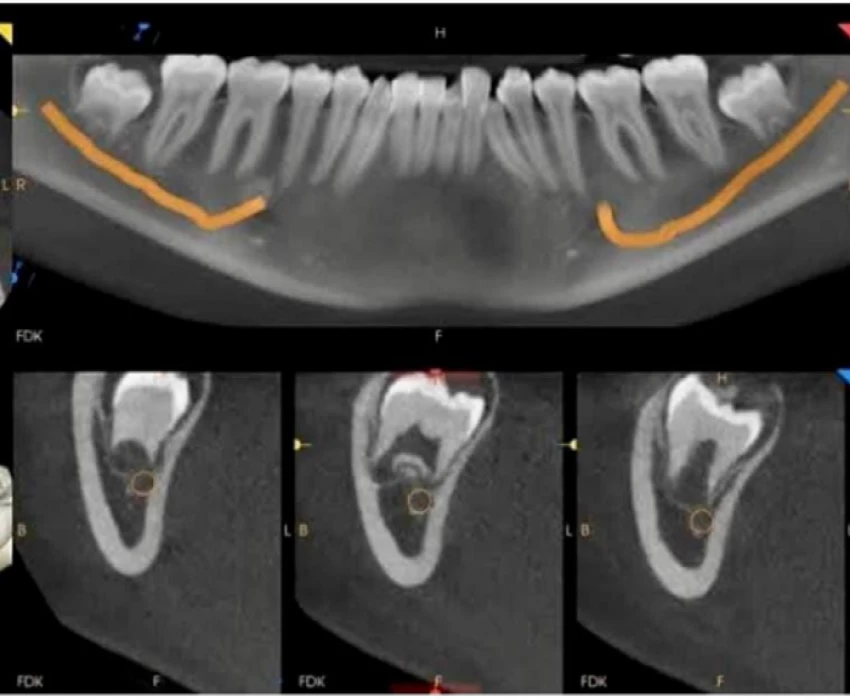

Over the past three decades, dentistry as a whole has made enormous strides. With these developments, it is now essentials to use more accurate diagnostic tools, particularly imaging techniques, keeping that in mind Dr. Tanmay has adapted modern dentistry in the form of advanced imaging methods including computed tomography, cone beam compute tomography, magnetic resonance imaging, and ultrasound along with all the conventional techniques.

The transition from analogue to digital radiography has simplified and sped up the procedure while also making image modification, storage, and retrieval simpler. The intricate craniofacial structures are now easier to examine thanks to 3-D imaging.

He has a wealth of knowledge in the interpretation of CBCT scans and has numerous papers and related research to his name.